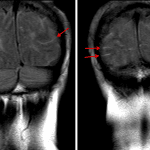

- FLAIR and diffusion signal hyperintensity in several bilateral cerebral sulci as well as layering in the occipital horn of the left lateral ventricle

- Subarachnoid hemorrhage (SAH)

FLAIR and diffusion signal hyperintensity in several bilateral cerebral sulci as well as layering in the occipital horn of the left lateral ventricle, which may represent trace subarachnoid hemorrhage, tumor dissemination, or proteinaceous material/exudate in the setting of meningitis. Recommend correlation with CSF analysis.